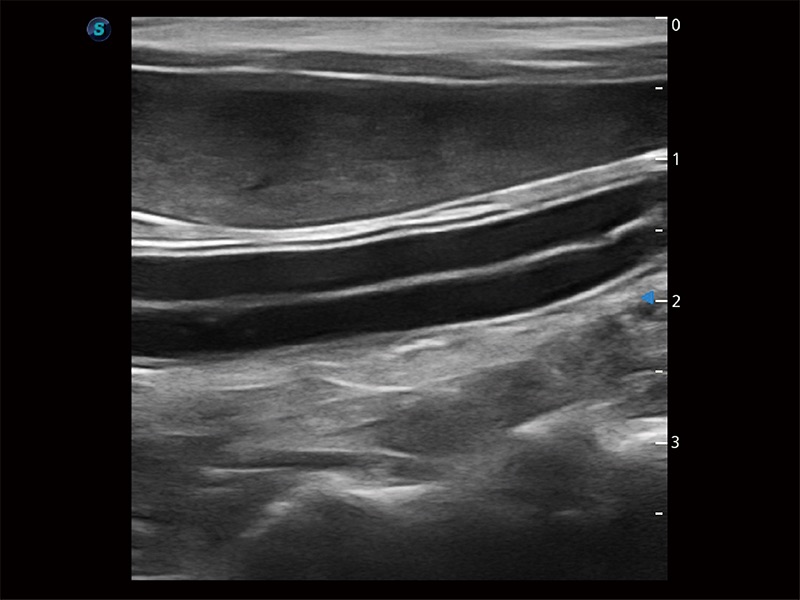

极大提升超低速微细血流的检出能力,同时更精准地滤除软组织和超声信号,为兽用医生提供以往无法通过常规血流获得的疾病诊断信息。

在传统二维血流成像的基础上,呈现血流的立体感,具有动感的生命力之美。即便是微小的血管也能轻松应对,提高了血流的视觉敏感性。